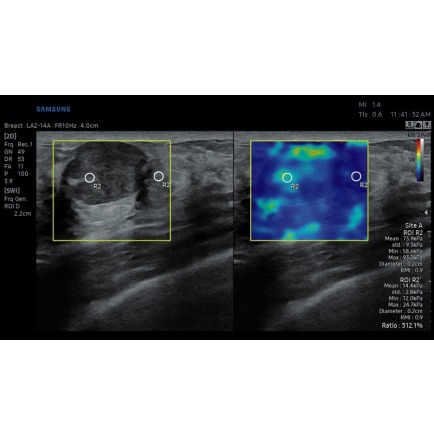

S-Detect for Breast – автоматически оценивает и формирует отчет по результатам исследования молочной железы.

S-Shearwave Imaging – эластограмма с цветовой кодировкой для изучения жесткости тканей.

Новообразование молочной железы в режиме S-Shearwave Imaging (эластография сдвиговой волной), линейный датчик 2-14 МГц